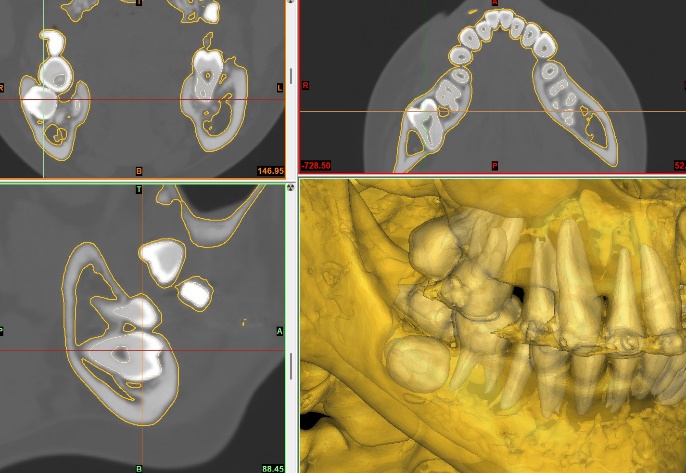

侵襲度の高い親知らずなどの抜歯に対しては、CT検査による精密な診断を行い、安全かつ適切に治療を進めます。全身疾患を有する患者様については、他科と連携しながら全身管理下で対応いたします。また、不安の強い方には、全身麻酔や静脈内鎮静法下で抜歯を行うことも可能です。

手術シミュレーションソフトによる画像(第二大臼歯、親知らずの埋伏)